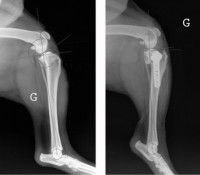

L’arthrite s’installe très rapidement (quatre semaines en moyenne) à la suite de la rupture du ligament croisé. Des radios de l’articulation sont donc souvent nécessaires pour évaluer le niveau d’atteinte. Elles permettent aussi de détecter une éventuelle lésion du ménisque, et localiser d’éventuels fragments d’os s’étant décrochés du tibia lors du déchirement. Là aussi, une anesthésie générale est nécessaire pour éviter que le chien ne bouge pendant le processus.

La chirurgie bénéficie d’un pronostic très bon à excellent (85 à 90% de réussite) lors d’une prise en charge précoce. En revanche, lorsque les soins sont différés et/ou lorsque le ménisque a subi une lésion, l’installation de l’arthrose influe négativement sur le pronostic.

Les techniques fondées sur une ostéotomie (coupe osseuse) modifient la biomécanique de l’articulation du genou en changeant l’action des muscles sur le haut du tibia. Elles présentent de meilleurs résultats chez les grands chiens, et permettent de réduire la progression de l’arthrite, qui n’en reste pas moins inévitable.

Elles conduisent à l’implantation d’une plaque osseuse de pontage et de vis qui ne seront plus nécessaires après la guérison, mais ne seront que très rarement retirées.